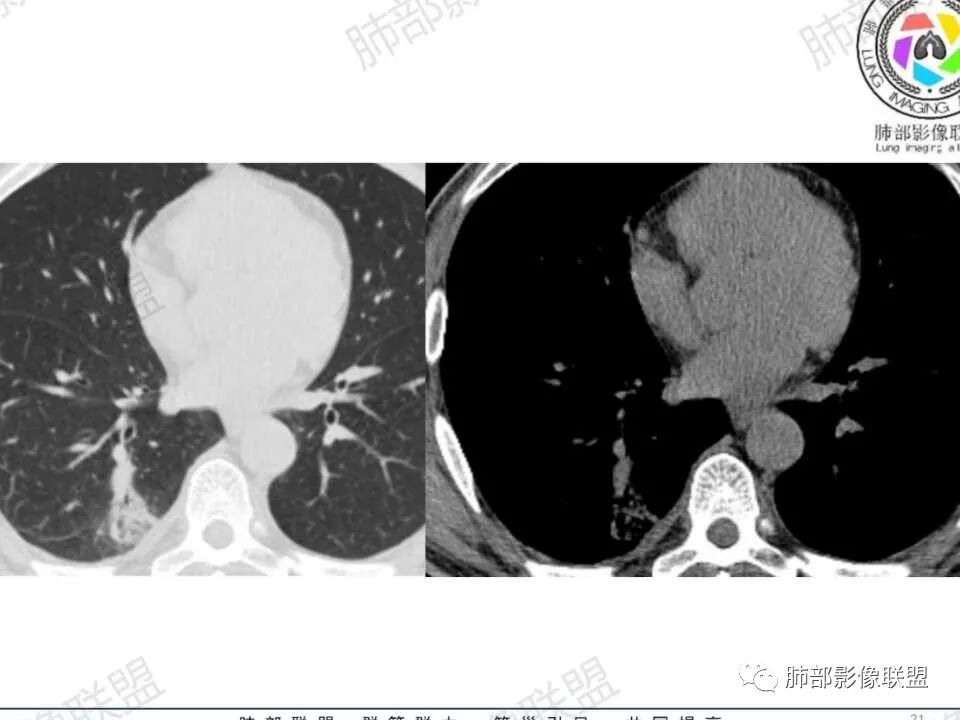

第一次CT:右肺下叶实性结节,近段血管束增粗并与结节相连,结节边缘光滑,密度均匀。第二次(间隔九天,治疗后复查):结节增大,伴有磨玻璃,边界欠清,远端树丫,结节内可见空泡影,壁光滑,临床无明显症状,短期增大先考虑非肿瘤性病变,炎性假瘤,结核,隐球菌。

中年男性患者,1年前发现肺结节,7天前复查结节较前增大,有糖尿病且控制不佳,胸部CT:右肺下叶后段类圆形结节病灶,边界清楚,内部密度均匀,治疗后见内壁光滑的小空洞,结节远端有阻塞性炎症,考虑炎性病变,结核可能,鉴别鳞癌。

右肺结节,气管堵塞,结节边缘光滑,密度均匀,远端斑片影。治疗后复查结节增大,空洞,斑片影伴有磨玻璃,边界欠清,糖尿病,短期增大,考虑结核,隐球菌。